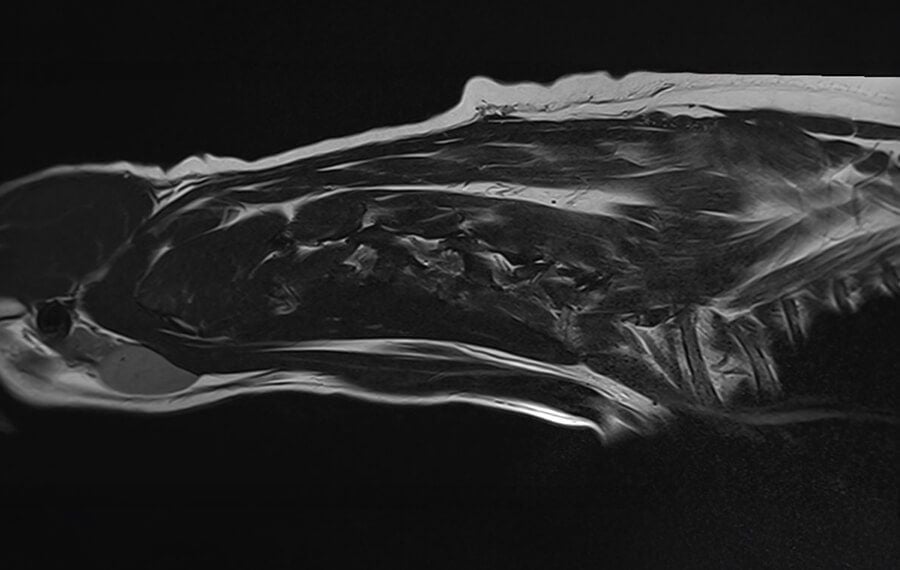

While X-rays can show the outline of the spine, they cannot show the spinal cord or the discs clearly.

For that reason, MRI (Magnetic Resonance Imaging) is considered the gold standard for diagnosing IVDD because it shows both the spinal cord and surrounding soft tissues in great detail. It helps us determine not only where the disc problem is, but also how severely the spinal cord is affected, which can guide prognosis and treatment choices.

Because dogs must remain perfectly still during the scan, MRI is performed under general anaesthesia for safety and accuracy.

While CT scans and CT or Xray myelographies can be helpful in certain cases, they cannot match MRI’s accuracy or its ability to assess spinal cord health. Choosing MRI means the best chance for an accurate diagnosis, tailored treatment, and a faster path to recovery for your dog. Also, myelography carry a slightly higher risk of side effects such as seizures.